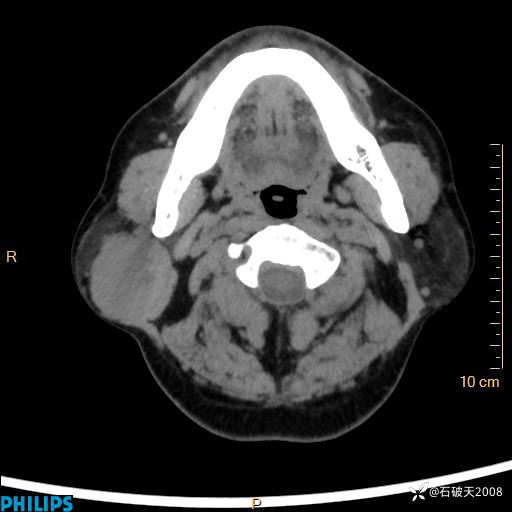

病例分享:颈部占位,一周后公布病理

男 57岁 主 诉:发现右侧颌下肿物1月余。

现病史:1月余前家属发现右侧颌下肿物。局部皮肤无红肿、热痛,无吞咽困难,无异物感,无恶心、呕吐,无头痛、头晕,无胸闷、胸痛,无发热、咳嗽、咳痰及呼吸困难。于我院行体表肿块彩超检查(2024.03.15我院)示:右侧耳下皮下软组织内低回声,未治疗。今为进一步治疗门诊以“腮腺肿瘤”为诊断收住我科,发病来患者神志清,精神可,饮食、睡眠及大小便正常,体重无明显下降。

平扫